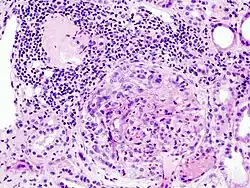

Mikroskopisch

Das histologische Bild ist bunt, da die Erkrankung schubweise verläuft. Typisch ist die ausgeprägte Halbmondbildung in den Glomeruli. Weiterhin sind einzelne Monozyten zu finden. Die Umgebung des Glomerulus ist meist entzündlich infiltriert. In der elektronenmikroskopischen Aufnahme zeigen die Gomerulusschlingen sich rupturiert und der Kapselraum des Glomerulus ist mit Fibrin ausgefüllt. Mit einer bestimmten Färbemethode, der Immunfluoreszenz, lassen sich die Anlagemuster der Immunglobuline nachweisen. Dies wird benutzt, um die verschiedenen Formen der RPGN zu unterscheiden (s. u.).